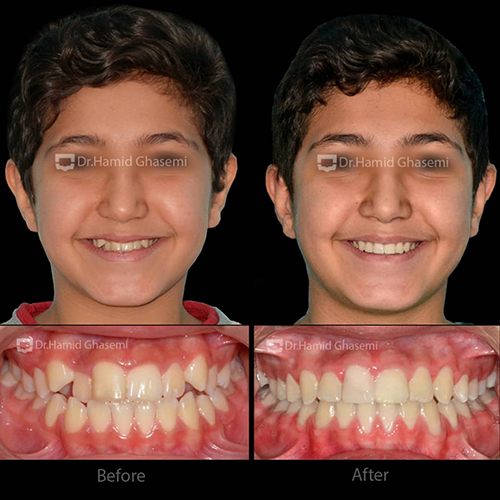

- حجم به هم ریختگی دندانهای بالا

- کمبود نمایش دندانهای فک بالا در لبخند به علت کمبود رشد فک بالا

در مرحله دوم، درمان ارتودنسی ثابت با استفاده از براکتهای دیمون استفاده شد. انتخاب براکتهای دیمون جهت عریض کردن قوس فکی و دندانی انجام شد که تأثیرات آن بر عریض شدن لبخند بیمار بسیار مشهود است.

- عریض شدن فک بالا

- از بین بردن باکال کریدور (Buccal Coridor) و در نتیجه افزایش نمایش دندانها در حین لبخند

- اصلاح انحراف میدلاین دندانی فک پایین

- اصلاح رابطه دندانی و فکی همراه با اکلوژن ایدهآل